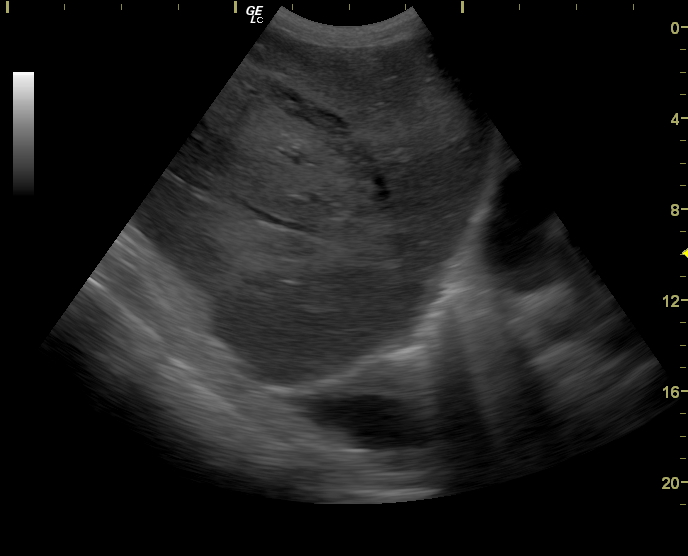

Добавлю еще пару случаев

Краевой разрыв с гемоперитонеумом (вне поля сканирования)